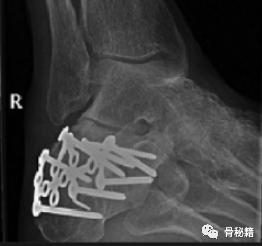

跟骨骨折的 X 线评估主要包括对侧位片和轴位片,Broden位片的测量。

1. 侧位像。在侧位片上有 2 个非常重要的影像学标记

Böhler’s 角:评价跟骨高度和关节压缩情况;

Gissane’s 角:评价跟骨前、中和后关节面的相对位置改变。

2. 轴位片。主要用于评价跟骨外翻畸形程度、宽度、后关节面的塌陷及与跗骨窦的相对位置。

3.Broden位片 可评估跟距后关节面的较好方法,用于术中评估关节面骨折复位情况;